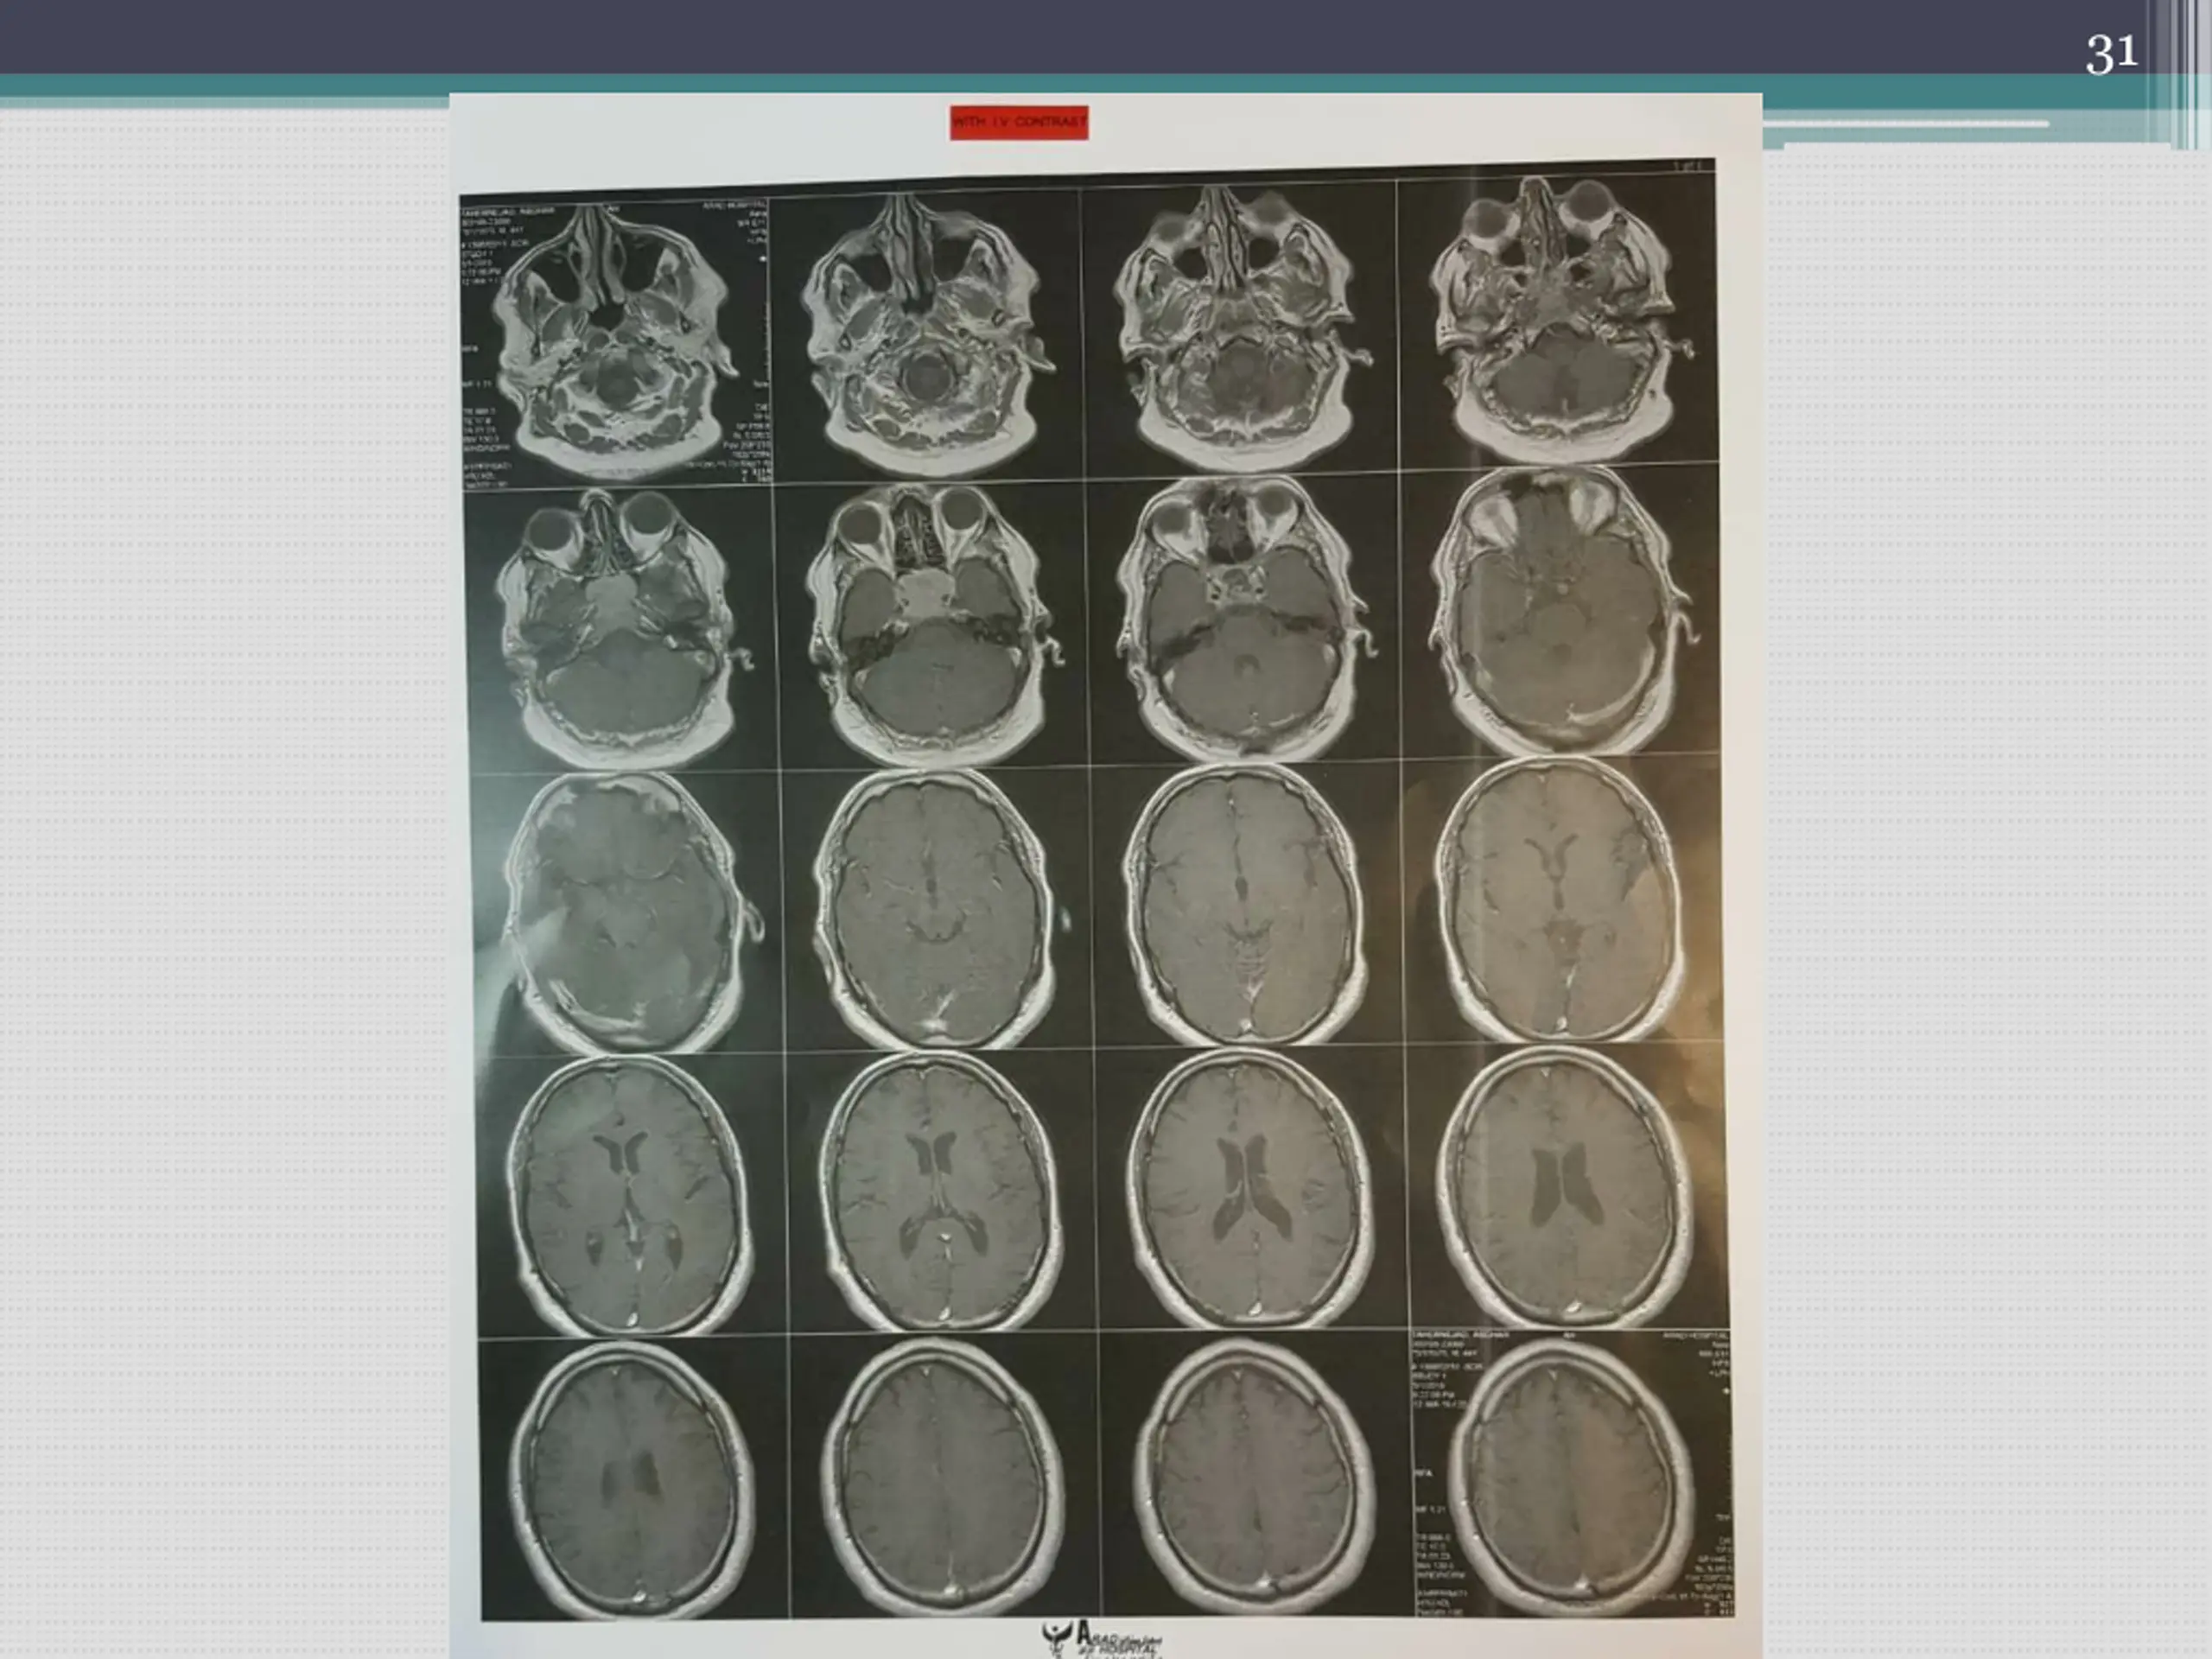

17 The patient continued cabergolin administration and at 25.1.98 referred to the physician due to progression of headache severity. Cabergoline dose reduced to 2mg/week Pituitary MRI was taken again

23 Report : 25/2/98 Large abnormal signal in the region of the body of sphenoid with extension to the clivus and mild parasellar extension without suprasellar extension, without shadow of pituitary gland measuring about 46mm in AP diameter, 14.6 mm in height and 33 mm in transverse diameter iso on T1 and mix mildly high and iso on T2 with homogenous enhancement after IV Gd. Could be due to invasive macroadenoma, however neoplastic lesion of the body of sphenoid such as chondroma could be considered in differential diagnosis. Overhanging of optic chiasma indicatining insufficiency of sella diaphragm. Suprasellar chiasma intact. Cavernous sinuses unremarkable.